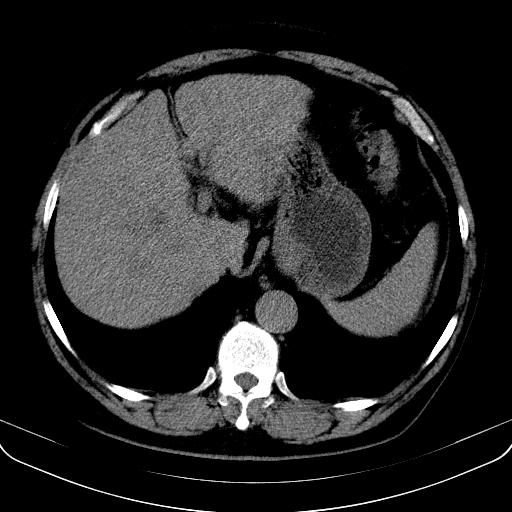

以下是引用jia119在2008-3-5 13:31:00的发言:[br]肝内多发片状低密度影,密度不均,我还是考虑肝ca可能,另肝内小囊肿,胆囊增大。

以下是引用形影不离在2008-3-5 12:18:00的发言:[br]肝硬化伴门脉高压征,肝内占位待排,增强再说.

以下是引用随光逐影在2008-3-5 21:11:00的发言:[br]肝硬化伴门脉高压(食管下段静脉曲张),肝癌不排除。建议:行ct增强扫描检查。

以下是引用同在2008-3-5 13:56:00的发言:[br]考虑肝癌可能性大,胆囊增大.